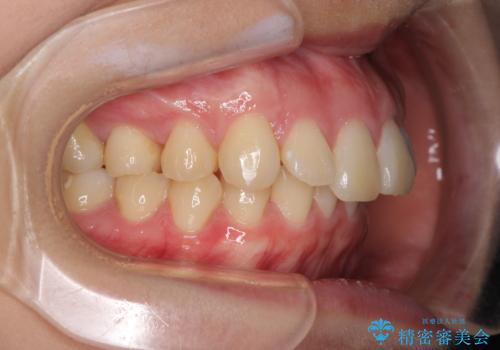

上顎前突 目立たないワイヤー装置での抜歯矯正

- 口元の突出感改善を希望して来院された患者様です。

口元を積極的に引っ込めるために、上下左右の小臼歯計4本を抜歯することとしました。

咬み合わせが深いため、咬み合わせの高さを向上させながら口元を下げることとしました。

左右ともに下顎に対して上顎歯列が前方位にある上顎前突であったので、上顎歯列全体を後方に移動させることで上下咬み合わせを改善し、その上で抜歯矯正により口元の突出感を改善させていきました。